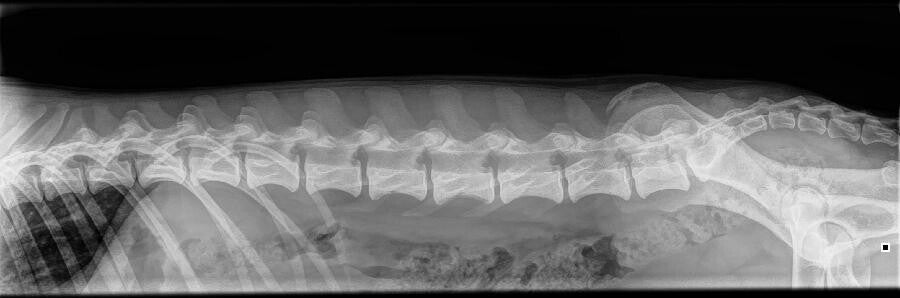

Dutch is een super lief en gevoelig jongetje die vooral geniet van aandacht, liefde en door het veld rennen. Er is start gemaakt aan agility maar nadat OCD werd geconstateerd zijn we hiermee gestopt. Tot op het punt van de röntgenfoto's hebben wij nooit een vermoeden gehad dat Dutch OCD zou hebben, en zeker niet aan beide schouders. Hij loopt niet mank en heeft geen verdere klachten, zijn bijnaam is 'Billie Bulldozer' omdat hij overal doorheen knalt en niet voorzichtig is met zichzelf. Vanzelfsprekend wordt met Dutch niet gefokt.

| OCD | Beiderzijds OCD (asymptomic OCD) |

| Spondylose | Vrij |

| LTV | Vrij |